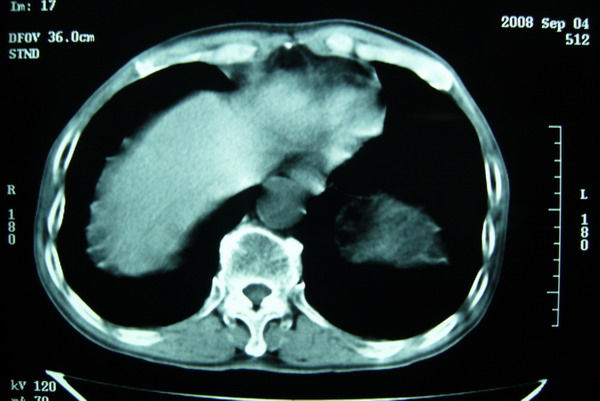

标题: CT15579:男 86岁 咳嗽 咳少量白痰 发热2天 吸烟史60年 [打印本页]

标题: CT15579:男 86岁 咳嗽 咳少量白痰 发热2天 吸烟史60年

右肺上叶巨大软组织肿块,轮廓不规则,纵隔内有肿大淋巴结,首先考虑肺癌。

右上肺一不规则团块,边缘有分叶和毛刺,纵隔有淋巴结肿大。右肺周围性肺癌首先考虑。